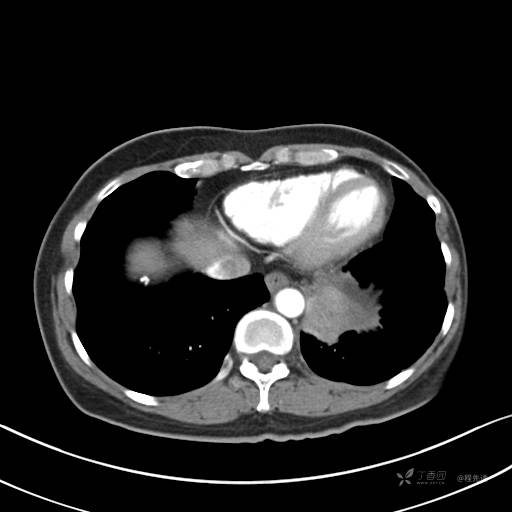

增强静脉期

静脉期CT值约84HU